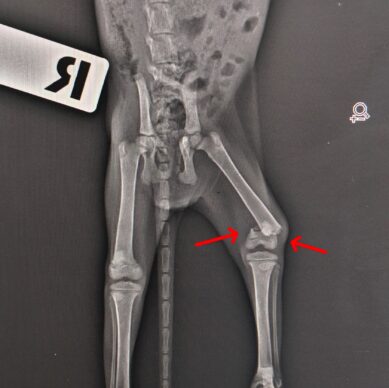

yavru kedi